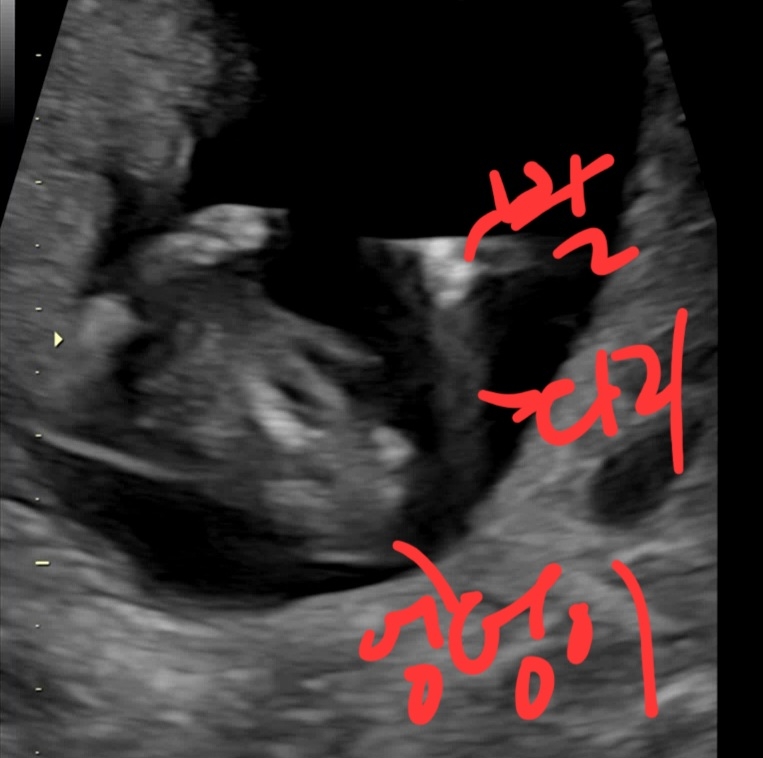

12주 성별 봐주세요(다른사진!!)

이번에는 중요부위 스쳐간 사진 가져왔어요 뭔가 존재감을 드러내는게 보이는데 작은것같기도하고.. 12주때는 딸도 나와있을 수 있다는데ㅜㅜ 성별 어떤것같아요? 참견해주세요ㅜㅜ